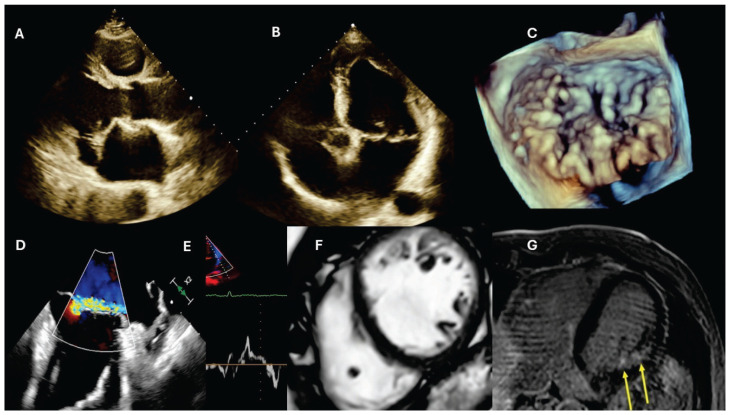

Unique coincidence of mitral valve prolapse and left ventricular hypertrabeculation in a patient with ventricular arrythmia.